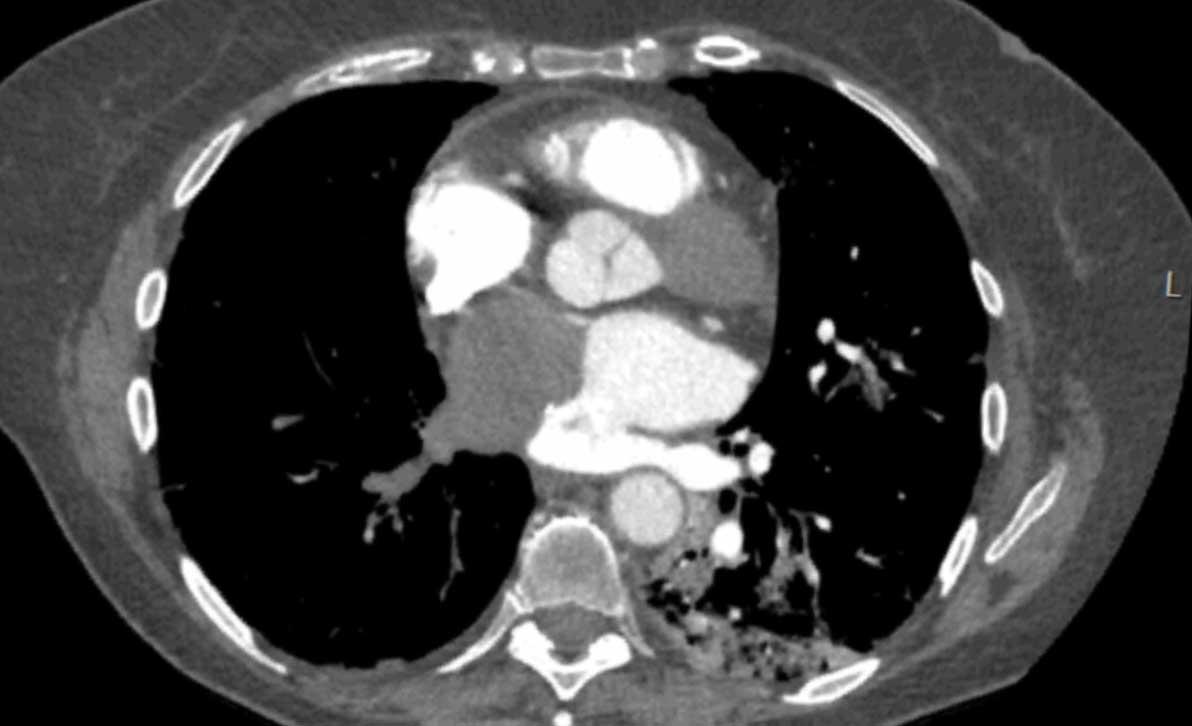

Hình ảnh

Tim ba buồng nhĩ trái (cor triatriatum sinistra) phát hiện tình cờ với hình ảnh ngấm thuốc muộn của ngăn phải nhĩ trái.

Trường hợp này ban đầu bị nhầm lẫn với huyết khối.

Tiếp tục xem hình ảnh MR…

Đây là hình ảnh MR của cùng trường hợp trên

Lấp đầy muộn của ngăn phải nhĩ trái trong tim ba buồng nhĩ trái (cor triatriatum sinistra).